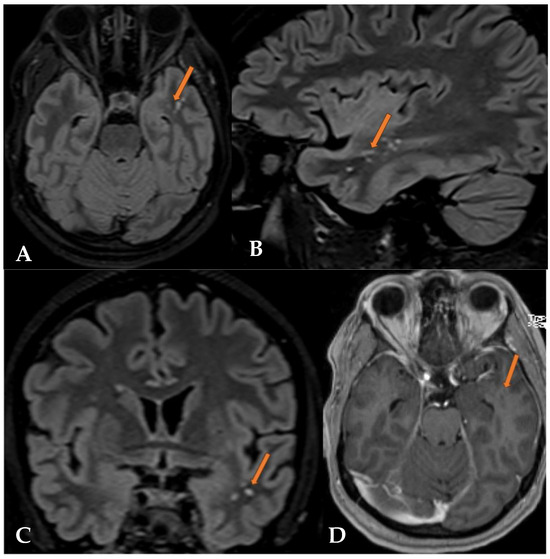

2.2. Case 2